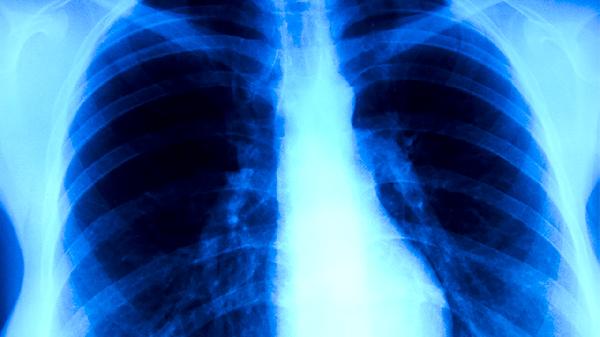

肺心病病因发病机制

肺心病的病因发病机制主要有慢性阻塞性肺疾病、胸廓运动障碍性疾病、肺血管疾病、睡眠呼吸暂停低通气综合征、原发性肺泡通气不足等因素引起,通常表现为呼吸困难、咳嗽、心悸、下肢水肿、意识障碍等症状。肺心病可通过氧疗、药物治疗、手术治疗等方式缓解。建议及时就医,积极配合医生治疗,在医生的指导下服用合适的药物,并做好生活管理。